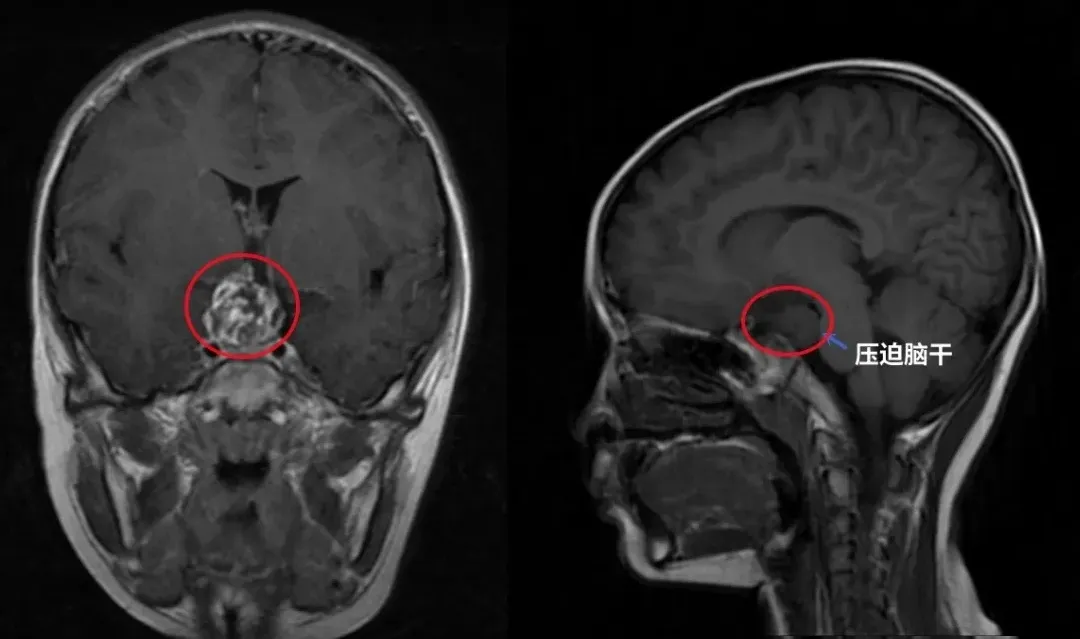

术前核磁影像

▼浩浩术前影像